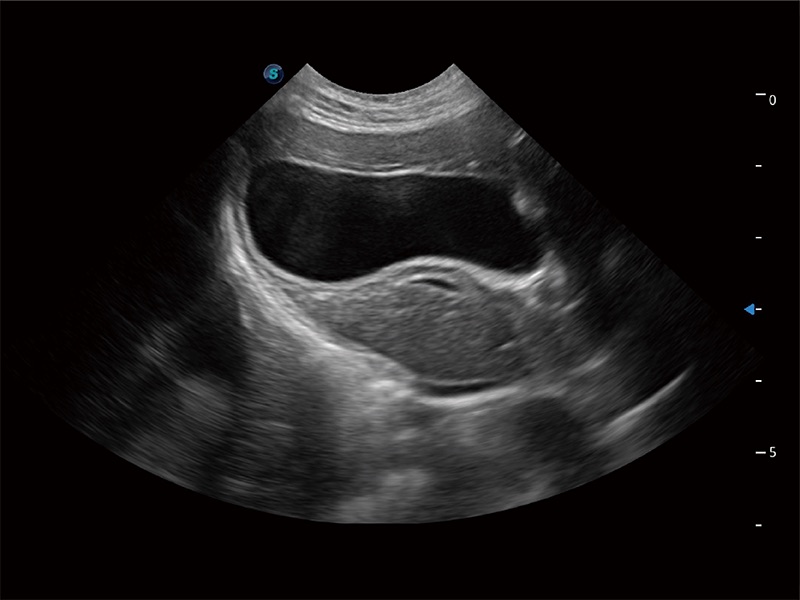

ProPet 80 配備了豐富的心臟探頭群、先進(jìn)的成像技術(shù)和專(zhuān)業(yè)的心臟測(cè)量工具,可幫助動(dòng)物醫(yī)生為不同體型和生理結(jié)構(gòu)的動(dòng)物提供心臟和心肌功能的全面評(píng)估。

能夠增加心肌組織與血流之間的區(qū)別。對(duì)于心臟掃查困難的動(dòng)物,可提供更好的心內(nèi)膜邊界的顯示。